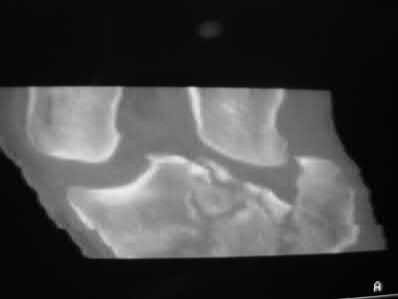

A 72-year-old woman falls down stairs and sustains the injury shown in Figure A. Additional radiographs are performed in Figure B to help assess the fracture pattern. These additional radiographs represent which of the following?

Additional traction radiographs are performed in distal humerus fractures to better understand the fracture configuration.

Traction radiographs help align the fracture fragments for better visualization. This is useful in comminuted fractures where distal fragments are telescoped or flexed on the proximal fragments, making CT scan visualization difficult.

Figures A and B show a distal humerus fracture without traction (A) and with traction (B) applied. Illustration A shows the same fracture after bicolumnar plating. Illustration B shows the different surgical approaches to the distal humerus (A, Campbell triceps splitting; B, O'Driscoll triceps reflecting anconeus pedicle [TRAP]; C, Bryan-Morrey triceps reflecting; D, olecranon osteotomy)